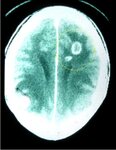

Toxoplasmose

Tomografia computadorizada: cérebro da toxoplasmose no sistema nervoso central

Do acervo de Louis M. Weiss, MD, MPH; uso autorizado